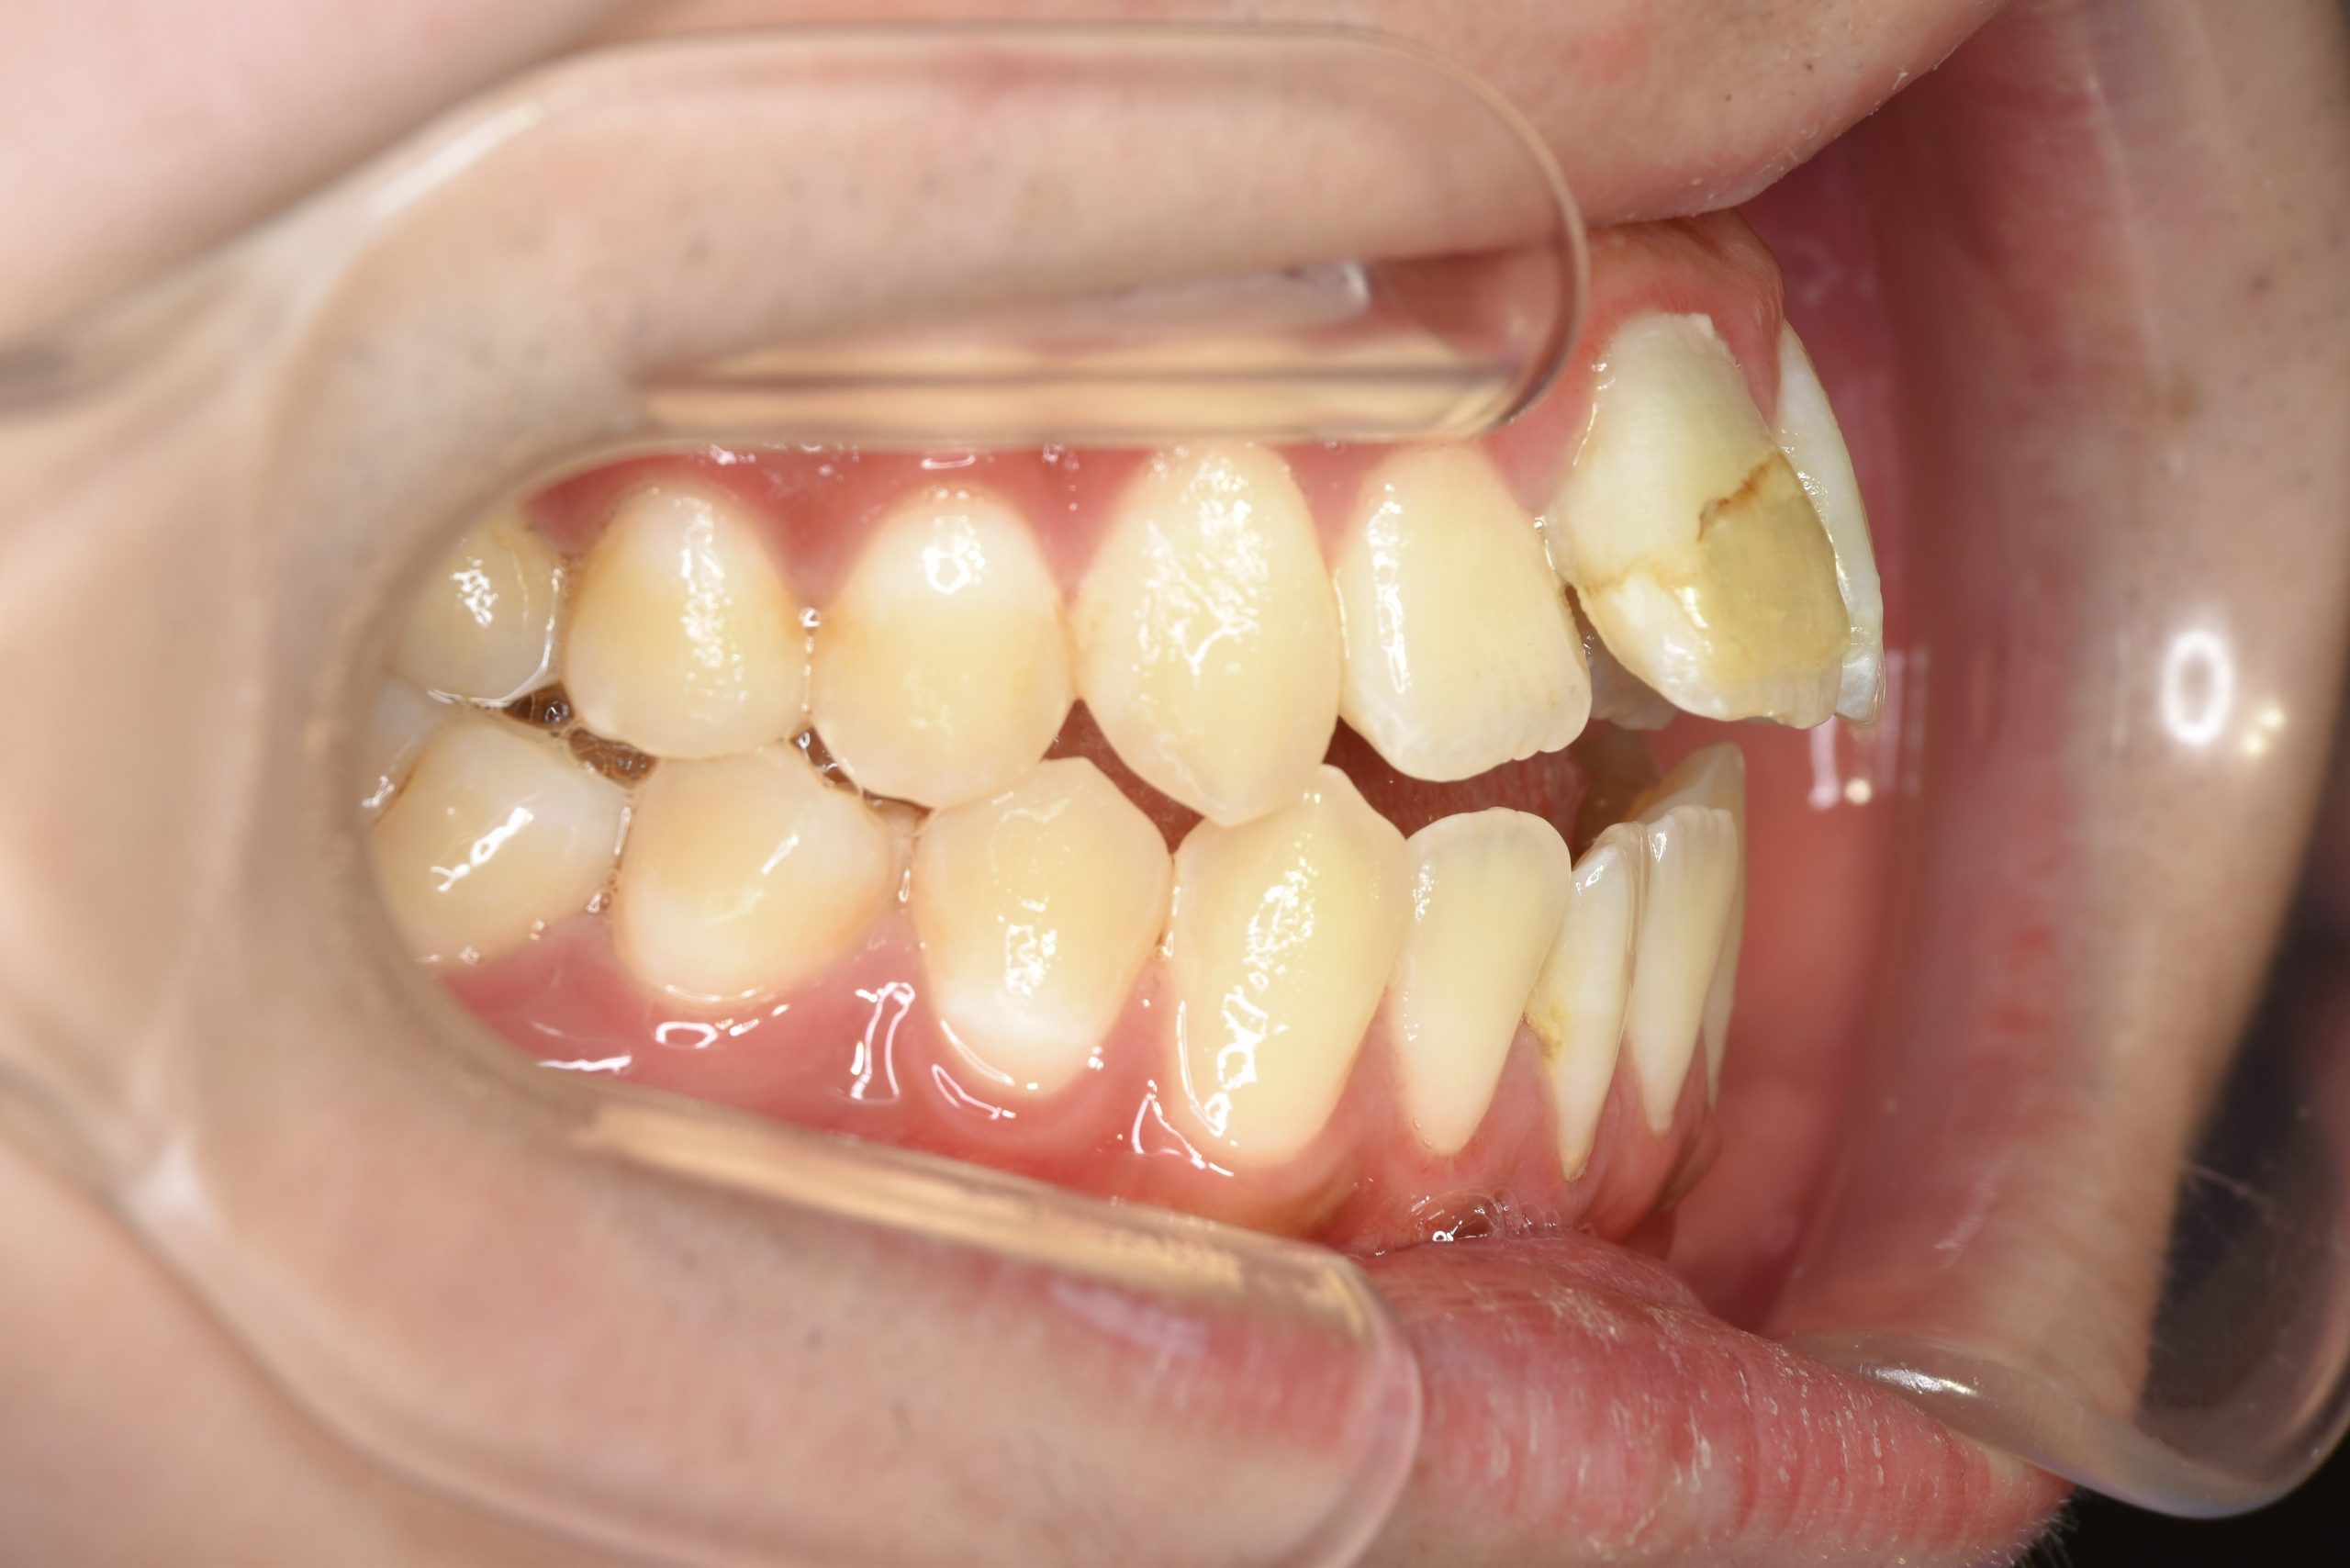

ビフォー

主訴 前歯が少し前に出ている|鼻づまり

施術内容 MSEと下顎リンガルアーチを用いて上下顎骨を拡大した。

その後をマルチブラケット装置を用いて非抜歯で歯牙を配列し、良好な咬合を獲得した。

治癒期間 1年6か月間